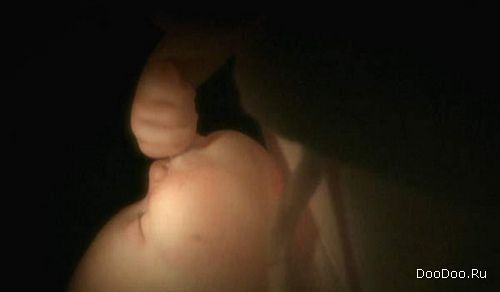

7 месяцев. Его мозг и спинной мозг полностью развиты. Мускулы его небольшого сердечка развиты, оно начинает биться немного спонтанно.

Последние дни беременности. Ребенок мечтает.